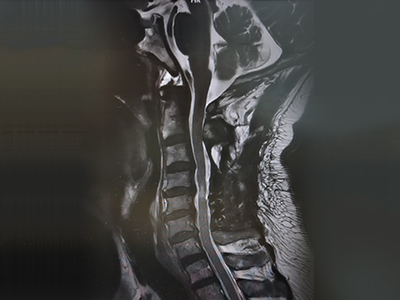

脊柱脊髓神经微创中心以微创技术为引领,以功能恢复为目标,主要治疗脊柱外伤、肿瘤、退行性病变、脊柱畸形等疾病。团队利用神经外科显微技术,结合神经内镜微创技术,对脊柱间盘变性疾病、颈腰椎管狭窄、颈腰椎间孔狭窄、颈腰椎间盘突出、颈腰椎体不稳、脊柱骨折、寰枢椎脱位、脊柱肿瘤、椎管内肿瘤、脊髓损伤、脊髓空洞、脊髓栓系等疾病进行高效、特色手术治疗,如颅颈交界区畸形寰枕减压内固定术、脊柱肿瘤全脊椎切除内固定术、微创椎管内肿瘤切除术、微创脊柱旁肿瘤切除术、寰枢椎脱位椎间融合内固定术、脊柱骨折微创经皮椎弓根钉内固定术、经椎间孔椎间融合内固定术(MIS—TLIF)等,最大程度降低脊柱脊髓手术创伤,具有创伤小、输血少、恢复快、口碑好,出院早等优势。

• 颈椎间盘切除、椎管减压术 6